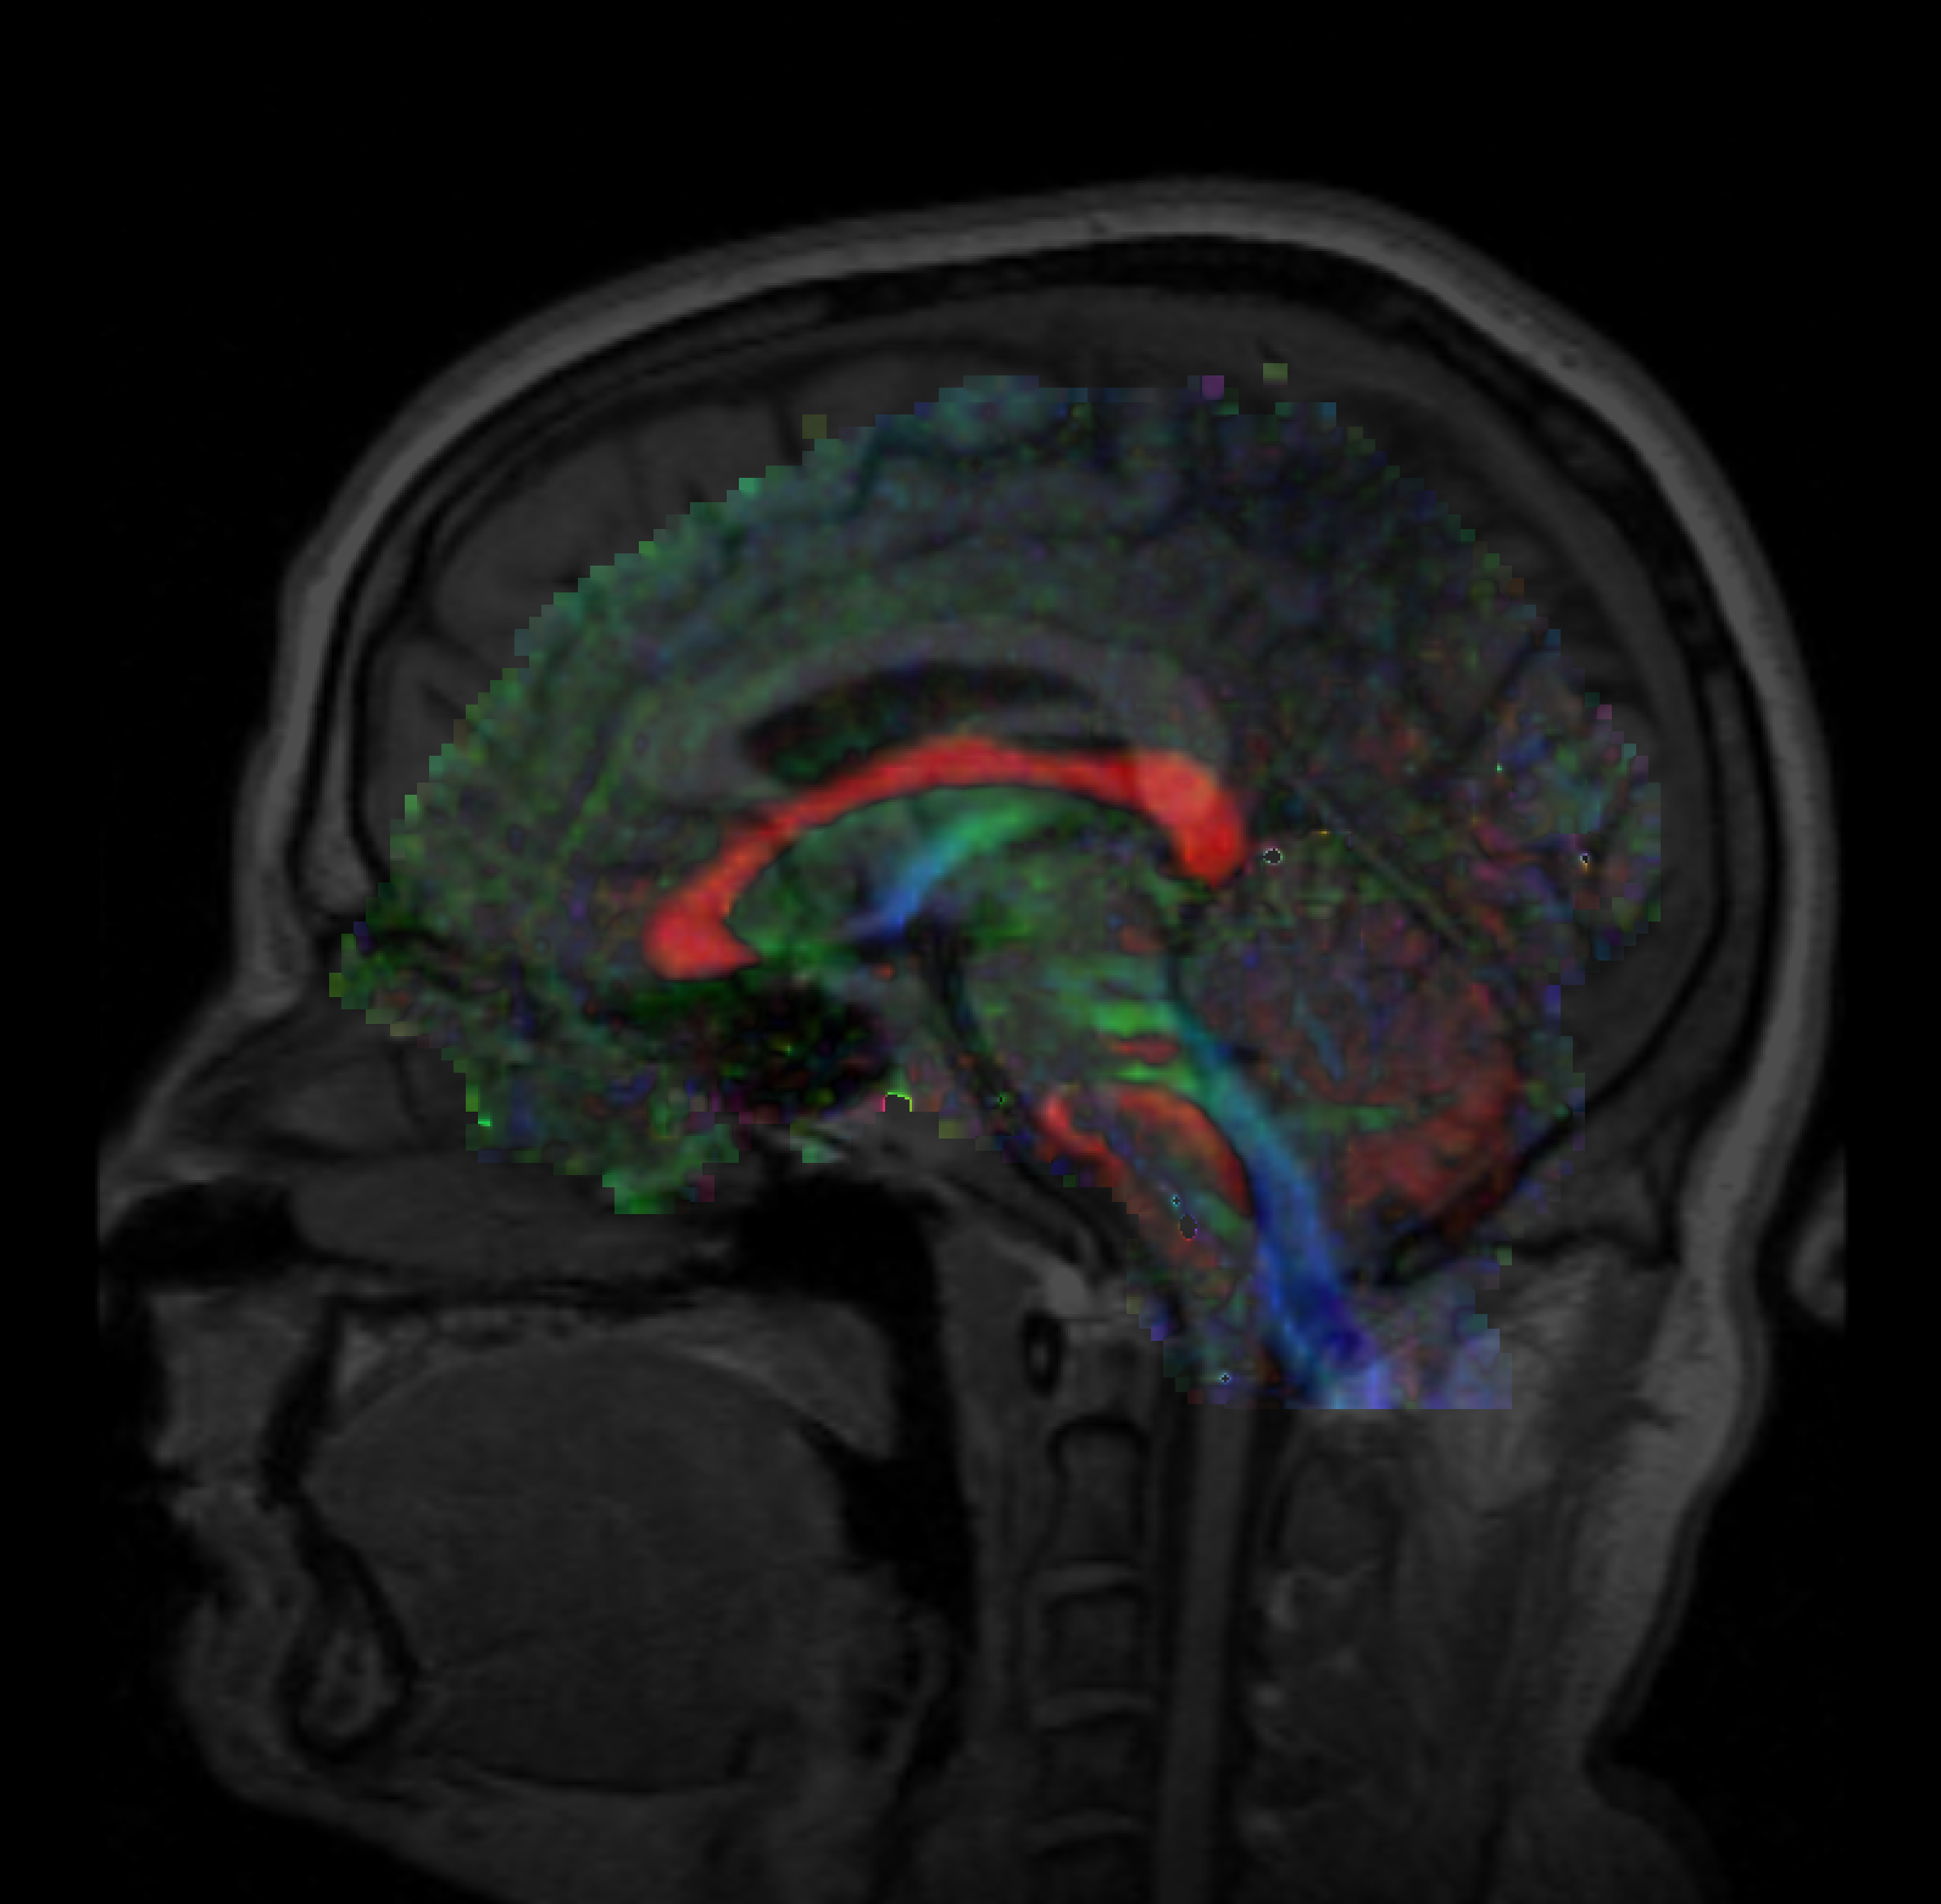

• (Successfully registered sample data using fiducials)

Unregistered.png File:Fiducials-pre-registration.png File:Fiducial-registration.png